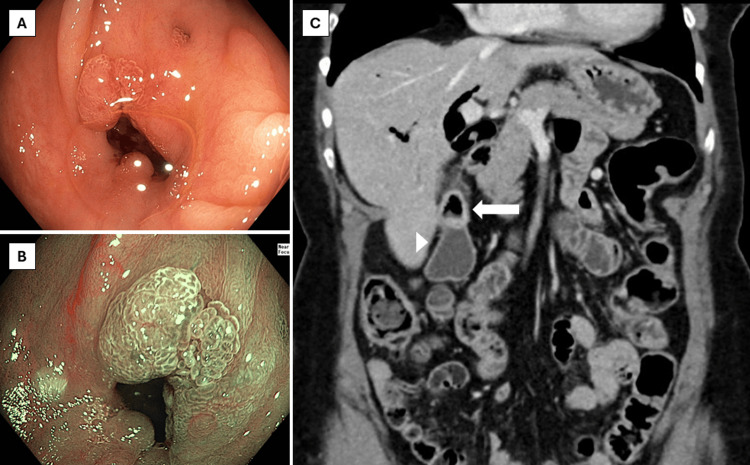

Ileocolonoscopy showed a normal mucosa of the terminal ileum and colon, apart from 1 diminutive adenomatous polyp in the sigmoid colon and diverticula throughout the colon. In the ascending colon, however, there was a diverticulum-like defect with tissue proliferation extending from the inside towards the borders of the defect with a chicken skin appearance of the surrounding mucosa (Figure 1). Endoscopic imaging with high-definition white light and virtual chromoendoscopy suggested reactive changes rather than a neoplastic process based on the vascular pattern. Biopsies from the aberrant area showed regenerative tissue, and random biopsies from the right and left colon excluded microscopic colitis. A contrast-enhanced computed tomography (CT) of the abdomen, which was performed a couple of days after the colonoscopy, showed marked pneumobilia with fistulisation between the ascending colon and gallbladder with signs of chronic cholecystitis. No radiopaque gallstones were described (Figure 1).